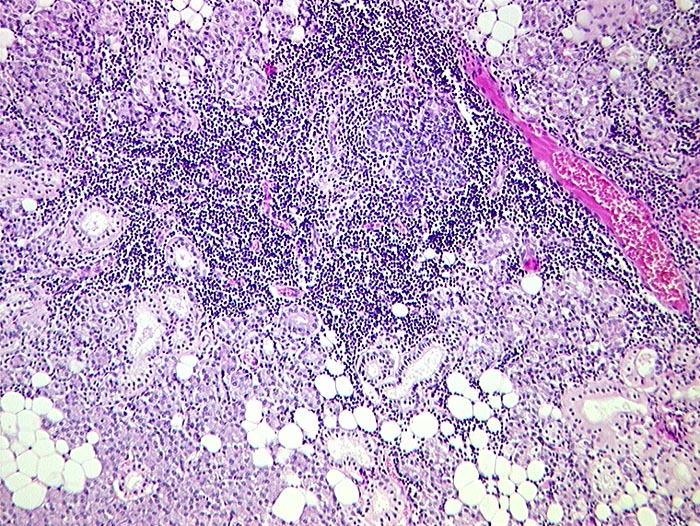

Das Zellbild ist je nach Stadium mehr oder weniger zellreich und zusammengesetzt aus Lymphozyten, Myoepithelien und selten Azinuszellen. Ein lymphozytäres Zellbild ist in Kombination mit dem typischen klinischen Bild (Keratokonjunktivitis sicca, Xerostomie, rheumatische Erkrankung) für die Sicherung der Diagnose ausreichend. Auf die Lippenbiopsie kann in diesem Fall verzichtet werden.